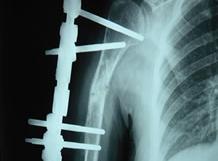

肱骨内髁骨折较少见,好发生于儿童,波及范围包括内上髁与滑车的大部分。受伤后肘内侧和内上髁周围软组织肿胀,或有较大血肿形成。临床检查肘关节的等腰三角形关系存在。患者表现为疼痛,特别是肘内侧局部肿胀、压痛、正常内上髁的轮廓消失。